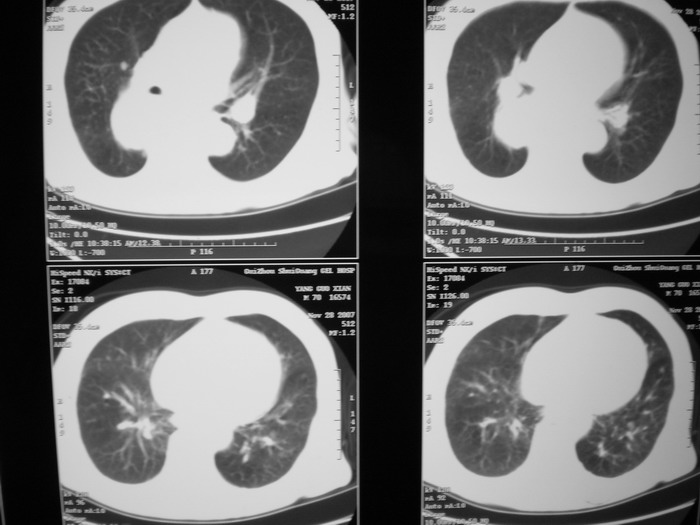

m、70y,反复咳嗽2月。请各位同仁给定位1、(肺?,纵隔?)2、定性。感谢!!

右后纵隔良性占位性病变,神经原性肿瘤可能性大,就其形态看,高密度囊肿待排,建议mri检查。

右下肺纵隔旁较大 均匀密度肿块,部分边缘植入纵隔,气管明显受压 变形。支持:后纵隔肿瘤!首选:神经源性!不支持肺内肿瘤原因:1 肿瘤位于下叶支气管及背段支气管开口区,但未侵犯支气管,只是受压表现。2 纵隔内未见肿大淋巴结。3 肺内未见阻塞性肺炎。

考虑右后纵隔良性肿瘤,以神经源性肿瘤可能性大。增强一下也能解决问题;神经源性肿瘤有明显强化。

支持后纵隔肿瘤,病灶大体呈“滴状”与支气管关系密切,考虑:1.高密度支气管囊肿,2.神经纤维瘤。增强有鉴别意义。